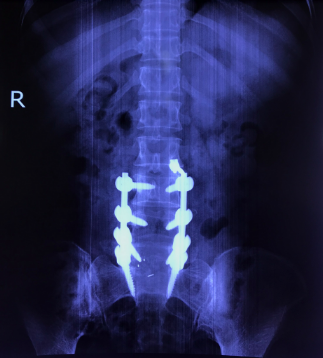

Sau khi hội chẩn, bệnh nhân được chỉ đỉnh phẫu thuật cố định cột sống và hàn xương liên thân đốt lối sau qua lỗ liên hợp (TLIF). 4 ngày sau phẫu thuật, bệnh nhân đã có thể ngồi dậy, tập đi lại trong khung tập đi, triệu chứng lâm sàng đã giảm đi rõ rệt: không còn cảm giác đau lan dọc 2 chân, cảm giác 2 chân trở nên nhẹ nhàng hơn, chỉ còn đau nhẹ vết mổ.

Hình ảnh: X Quang bệnh nhân sau phẫu thuật hàn xương, nắn chỉnh cột sống